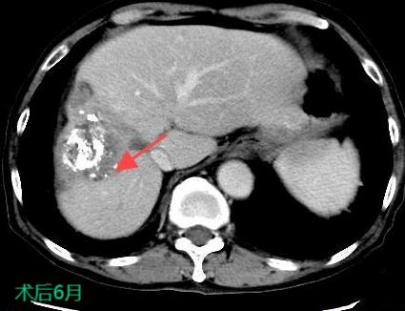

三、肝癌的介入治療

TACE/HAIC:經(jīng)肝動(dòng)脈灌注化療栓塞(TACE)、肝動(dòng)脈內(nèi)灌注化療藥物(HAIC)是在不開刀暴露腫瘤病灶的情況下,在皮膚上做直徑幾毫米的切口,在影像設(shè)備的引導(dǎo)下,導(dǎo)絲和導(dǎo)管插入肝臟腫瘤血管,注入栓塞劑和化療藥物使肝臟腫瘤內(nèi)化療藥物濃度提高,并減少全身的藥物總濃度,達(dá)到提高化療效果并減少毒副作用的目的。對于無法手術(shù)切除的巨塊型肝癌、肝內(nèi)多發(fā)肝癌病灶、肝癌結(jié)節(jié)破裂出血有良好的治療效果。

癌的介入治療

射頻熱消融被廣泛地用于原發(fā)性肝癌的治療,將電極針插入腫瘤通過射頻能量使病灶局部組織產(chǎn)生高溫,凝固腫瘤,近似于外科手術(shù)根治性切除的效果。

射頻熱消融治療